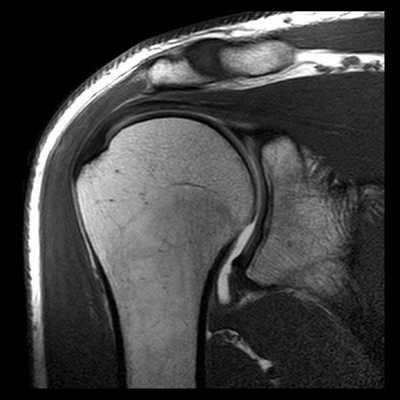

У каждого способа обследования имеются свои преимущества и недостатки. На сегодняшний день ведущую роль в визуализации вне- и внутрисуставных структур плечевого сустава играет МРТ, которая позволяет выявлять мягкотканные и костные повреждения в суставах. Она может осуществляться по двум базовым протоколам - бесконтрастная томография и МРТ плечевого сустава с применением парамагнитных контрастных веществ (она же МР артрография). Лидирующую роль в оценке состояния костей плеча играет спиральная компьютерная томография.

![МРТ плечевого сустава]()

Когда МРТ плечевого сустава лучше, чем КТ плеча

В медицинских центрах СПб обследование плечевого сустава с помощью магнитного резонанса является профилирующим диагностическим исследованием патологий суставных тканей. Именно МРТ плечевого сустава дает возможность получить данные о состоянии суставов, мягких тканей и хрящей. Томография плеча хорошо покажет:

- причины непонятной боли в плече, хруста в плече;

- последствия травмы в области плечевого сустава, перелома;

- место разрыва связок, периодических вывихов;

- причины припухлости в области плеча;

- ущемление нервов, сухожилий.

МРТ также позволяет отличить здоровые ткани от поврежденных при предположении на опухоль или раковые метастазы, помогает оценить картину травм и их месторасположение.

В отличие от КТ плеча, МРТ может многократно применяться при исследовании состояния здоровья детей и беременных женщин. По времени для проведения МРТ плечевого сустава может понадобиться от десяти до двадцати минут нахождения пациента в неподвижном состоянии в условиях замкнутого пространства камеры МРТ. КТ плечевого сустава занимает всего до десяти секунд, что по времени проведения исследования предпочтительно для людей, страдающих клаустрофобией или боязнью замкнутых пространств.